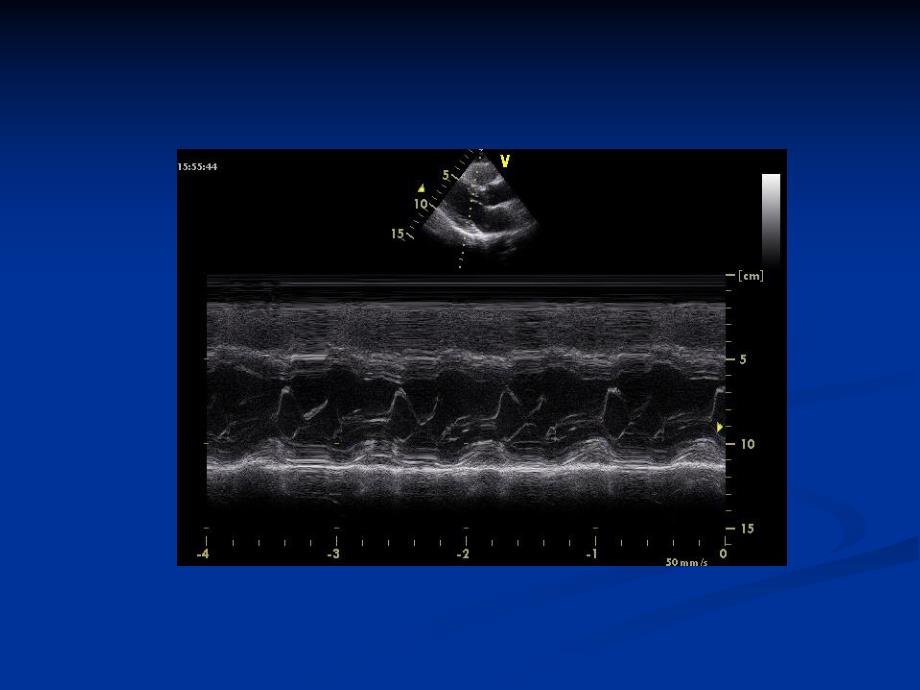

多普勒超声多普勒超声运动负荷运动负荷药物负荷药物负荷声学造影声学造影彩色多普勒超声成像彩色多普勒超声成像频谱多普勒频谱多普勒n频谱多普勒,可显示一维的血流信息,提供频谱多普勒,可显示一维的血流信息,提供血流动力学定量分析的重要资料,可分为脉血流动力学定量分析的重要资料,可分为脉冲多普勒和连续多普勒。冲多普勒和连续多普勒。n脉冲多普勒:采用间断发射和接收超声脉冲,脉冲多普勒:采用间断发射和接收超声脉冲,以中空频带频普图像显示血流信息,对血流以中空频带频普图像显示血流信息,对血流定位诊断。定位诊断。n连续多普勒:通过连续发射和接收脉冲以充连续多普勒:通过连续发射和接收脉冲以充填频谱图像显示血流信息。填频谱图像显示血流信息。